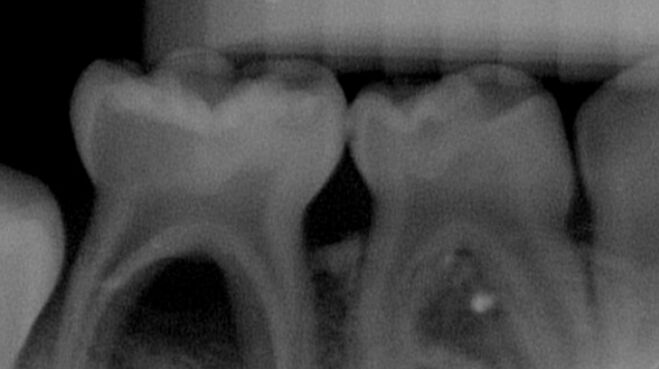

35.5歲男童右下牙齦反覆出現膿腫(abscess),所拍攝的放射線影像如圖示;關於治療方式,下列敘述何者錯誤? (A)第一乳臼齒可施行樹脂填補 (B)膿腫發生的主因是第二乳臼齒鄰接面齲齒 (C)第二乳臼齒可施行牙髓切除術(pulpectomy)或拔除乳牙 (D)考量到拔除第二乳臼齒可能造成空間喪失,牙髓切除術(pulpectomy)可能是較好的選擇